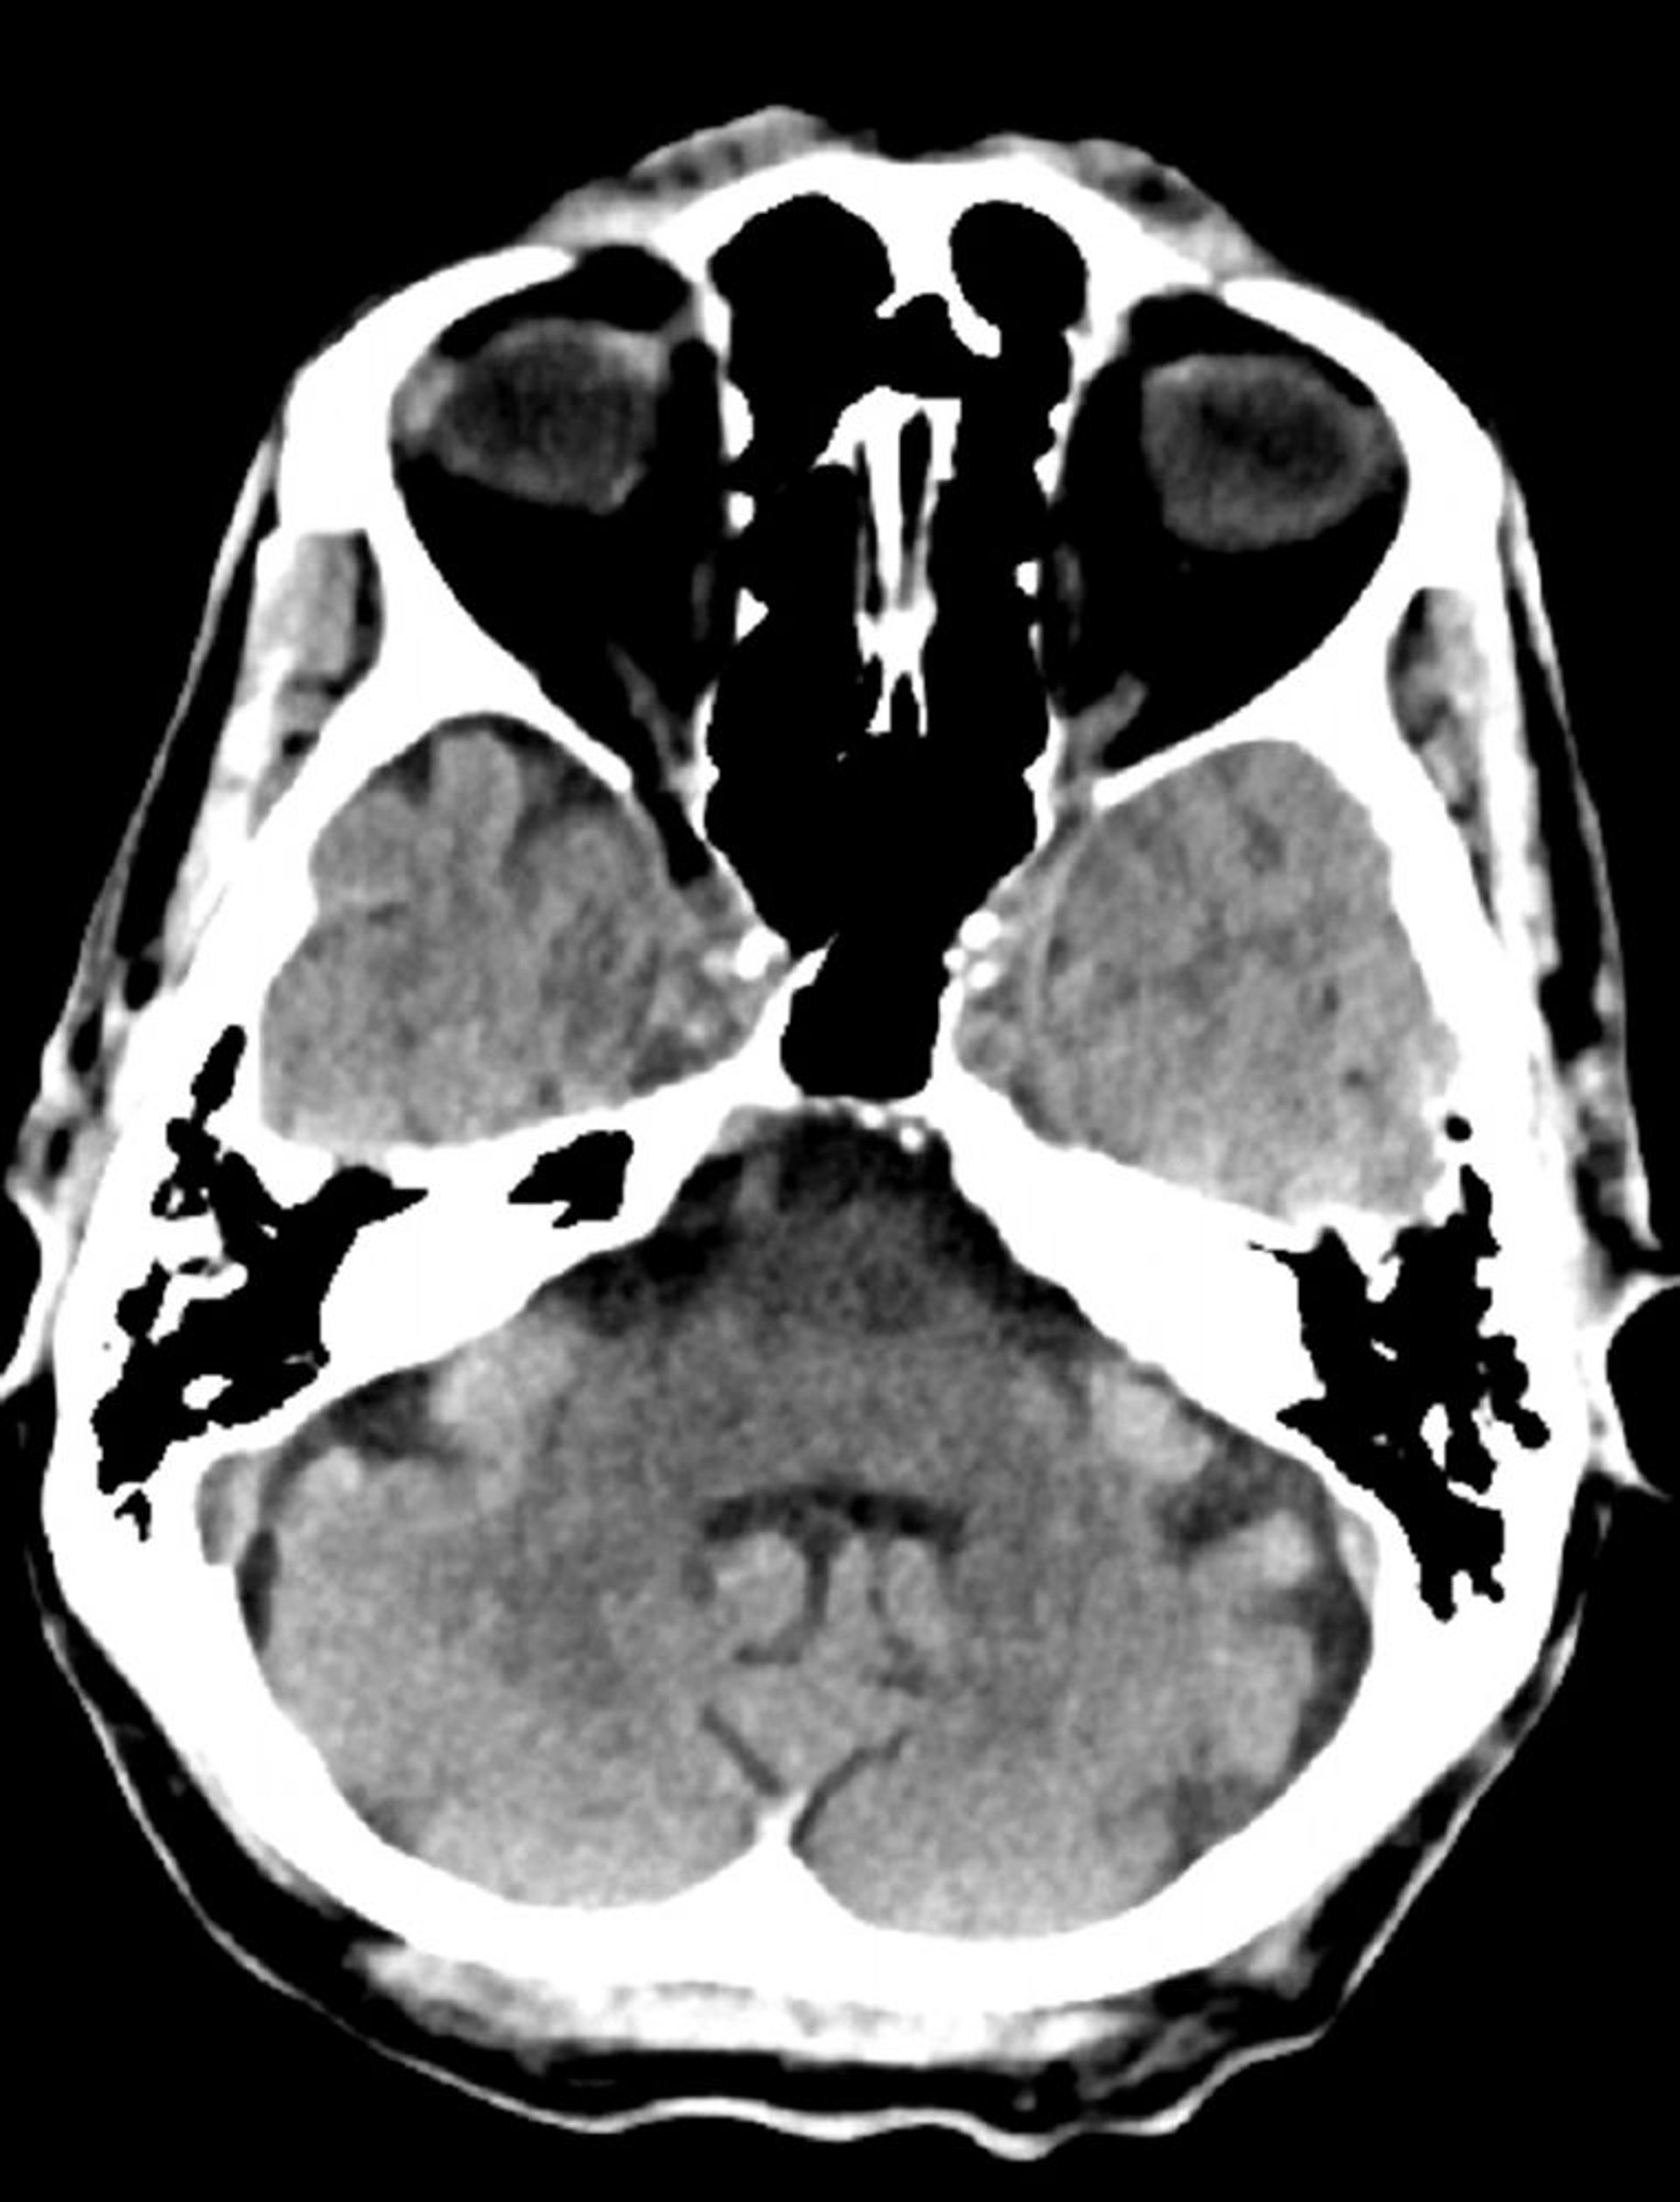

Normal Head CT Scan (Adult, Age 74) – Slide 8

This image is a normal CT scan of the head of an adult aged 74. When compared with the normal CT scan of the head of a 30-year-old, the ventricles and sulci are larger. These findings are normal in this age group.